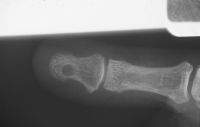

| Xrays of a painful glomus

tumor of many years duration, showing a local impression extending

through the dorsal and palmar cortices of the distal phalanx. |

| Bone defect filling in some

at this time. |